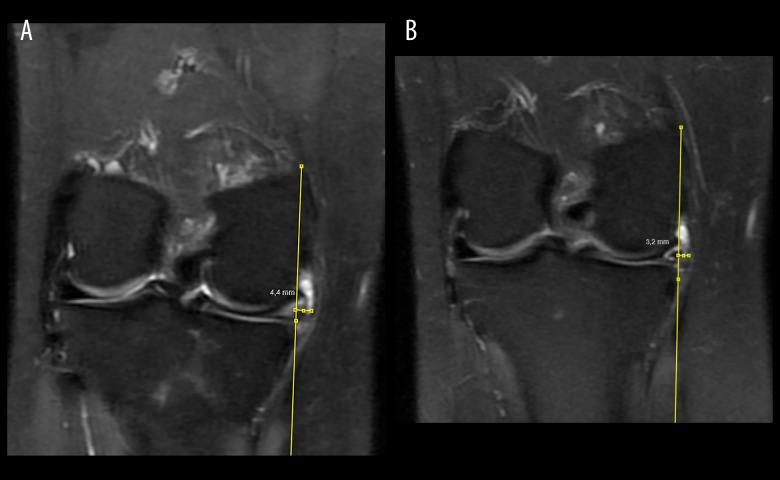

BACKGROUND This retrospective study from a single center in Turkey aimed to evaluate 2-year outcomes of 21 patients undergoing knee arthroscopic repair of extruded meniscus tears without root tear. MATERIAL AND METHODS The retrospective study comprised 21 individuals who underwent arthroscopic extruded meniscus repair and were followed up for at least 2 years. The study analyzed the meniscus extrusion amounts in preoperative and postoperative MRI scans, the Kellgren-Lawrence stages in knee radiographs, and the Lsyhom and The International Knee Documentation Committee (IKDC) scores of the included patients. RESULTS In this study, the repair operation extrusion levels were 3.30 mm from 4.01 mm preoperatively (P<0.001). After the repair, there was a significant increase in the Lsyhom and IKDC scores (P<0.001). According to the Kellgren-Lawrence scale, 12 patients were evaluated as stage 0, 6 patients as stage 1, and 3 patients as stage 2. According to the radiographs taken at the last follow-up, 2 patients progressed from stage 0 to stage 1, 2 patients progressed from stage 1 to stage 2, and 1 patient progressed from stage 2 to stage 3. CONCLUSIONS Arthroscopic treatment of extruded meniscus tears can enhance functional status and increase patients' functional status. Nevertheless, the absence of successful centralization extruded meniscus tears. This study discovered that radiological extrusion did not diminish beyond the critical threshold of 3 mm, which is associated with the development of osteoarthritis. This highlights the necessity of taking these elements into account when devising a treatment plan.

该回顾性研究纳入了 21 例接受关节镜下半月板挤压撕裂修复术的患者,随访时间至少 2 年。研究分析了术前和术后 MRI 扫描的半月板挤出量、膝关节 X 线的 Kellgren-Lawrence 分期以及纳入患者的 Lysholm 和国际膝关节文献委员会(IKDC)评分。

本研究中,修复术后的挤出水平从术前的 4.01mm 下降至 3.30mm(P<0.001)。修复后,Lysholm 和 IKDC 评分显著提高(P<0.001)。根据 Kellgren-Lawrence 分级,12 例患者为 0 级,6 例为 1 级,3 例为 2 级。根据末次随访时的 X 线片,2 例从 0 级进展至 1 级,2 例从 1 级进展至 2 级,1 例从 2 级进展至 3 级。